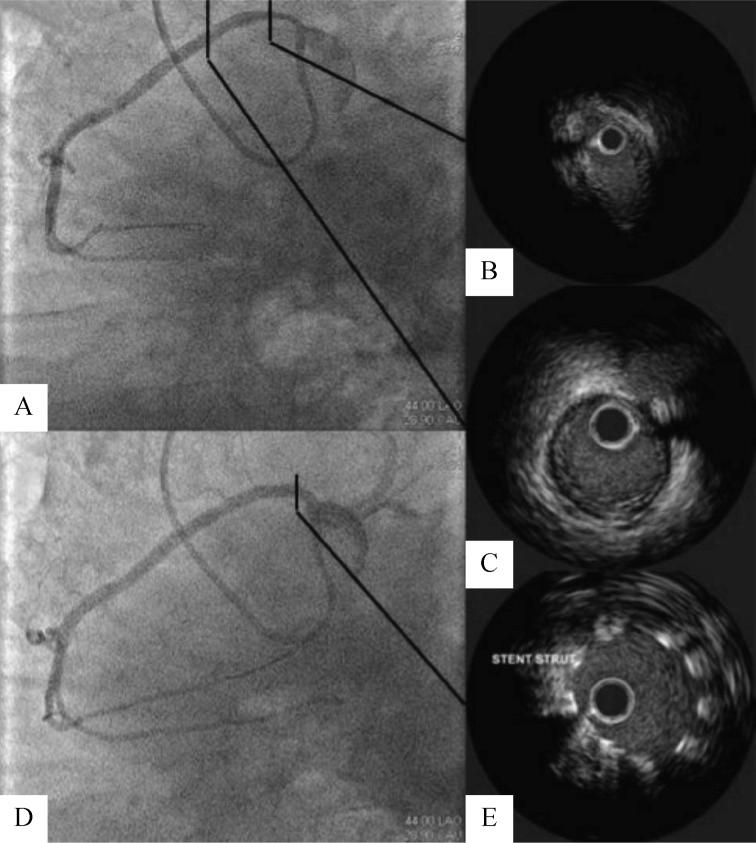

Coronary artery anomalies (CAAs) may be discovered more often as incidental findings during the normal diagnostic process for other cardiac diseases or less frequently on the basis of manifestations of myocardial ischemia. The cardiovascular professional may be involved in their angiographic diagnosis, functional assessment and eventual endovascular treatment. A complete angiographic definition is mandatory in order to understand the functional effects and plan any intervention in CAAs: computed tomography and magnetic resonance imaging are useful non-invasive tools to detect three-dimensional morphology of the anomalies and its relationships with contiguous cardiac structures, whereas coronary arteriography remains the gold standard for a definitive anatomic picture. A practical idea of the possible functional significance is mandatory for deciding how to manage CAAs: non-invasive stress tests and in particular the invasive pharmacological stress tests with or without intravascular ultrasound monitoring can assess correctly the functional significance of the most CAAs. Finally, the knowledge of the particular endovascular techniques and material is of paramount importance for achieving technical and clinical success. CAAs represent a complex issue, which rarely involve the cardiovascular professional at different levels. A timely practical knowledge of the main issues regarding CAAs is important in the management of such entities.

冠状动脉异常(CAAs)可能在其他心脏疾病的常规诊断过程中作为偶然发现而被更频繁地发现,或者更不频繁地基于心肌缺血的表现。心血管专业人员可能参与其血管造影诊断、功能评估和最终的血管内治疗。为了了解功能影响并计划对 CAA 进行任何干预,需要进行完整的血管造影定义:计算机断层扫描和磁共振成像是检测异常的三维形态及其与相邻心脏结构关系的有用非侵入性工具,而冠状动脉造影仍然是明确解剖图像的金标准。为了决定如何处理 CAA,需要对可能的功能意义有一个实际的了解:非侵入性应激试验,特别是有或没有血管内超声监测的侵入性药物应激试验,可以正确评估大多数 CAA 的功能意义。最后,了解特定的血管内技术和材料对于实现技术和临床成功至关重要。CAA 是一个复杂的问题,很少涉及不同层次的心血管专业人员。及时了解有关 CAA 的主要问题对于此类实体的管理非常重要。